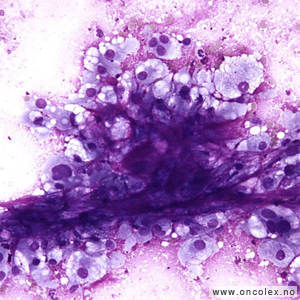

Cytologisk bilde av osteoblastisk osteosarkom. |

Klassisk osteosarkom

Klassisk osteosarkom ses hos unge i alderen 10–30 og sitter i metafysen i lange rørknokler, typisk rundt kneet og øverst i overarmen. Tumor viser malignt utseende celler som produserer osteoid og ben med forkalkninger. Det kan i tillegg ofte påvises områder med kondroblastisk og/eller fibroblastisk utseende. Dersom man ikke får representativ biopsi kan man feilaktig stille diagnosen kondrosarkom eller fibrosarkom på et slikt materiale.